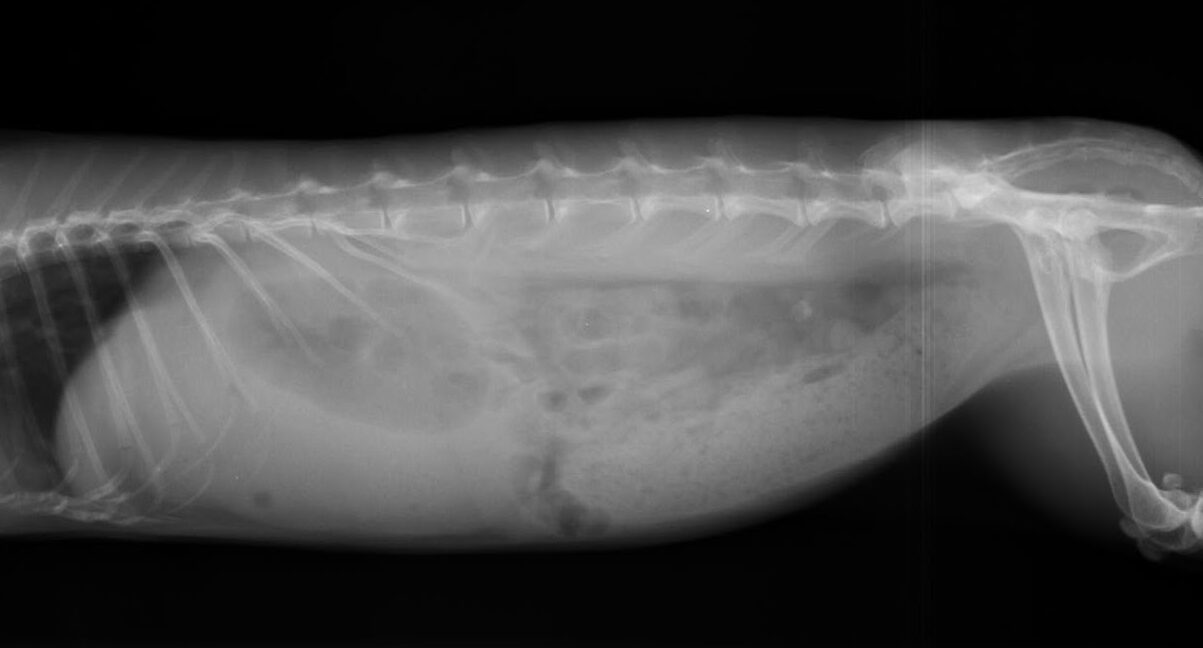

レントゲン検査 胃の大きさや内容物の状態、小腸・盲腸のガスの溜まり具合を確認します。鬱滞を引き起こす別の病気がないかどうかも確認します。

レントゲン写真① レントゲン写真②